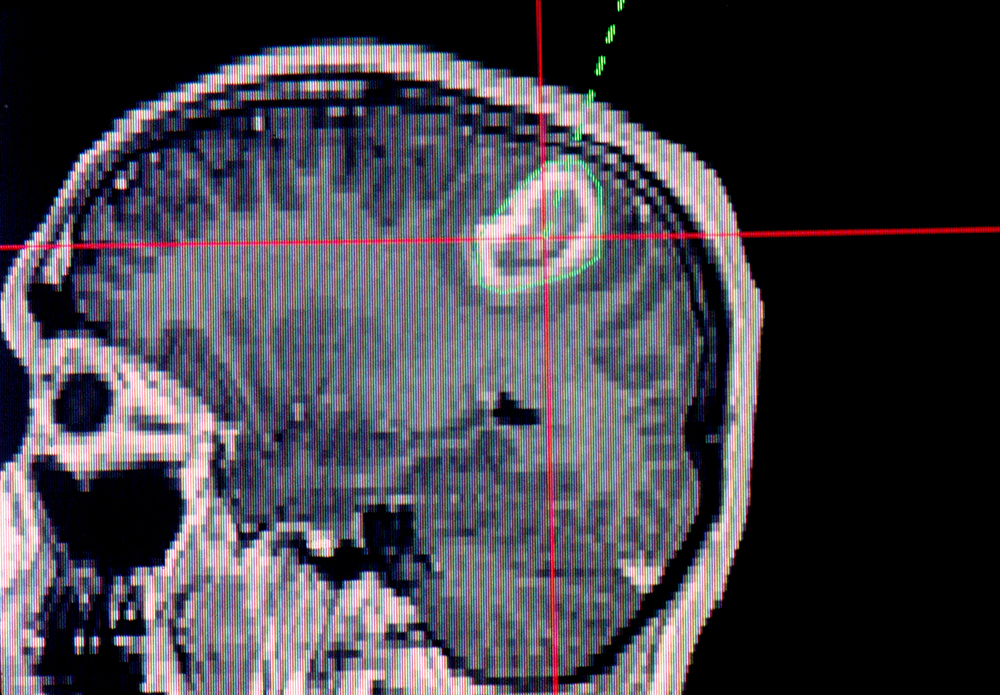

A magnetic resonance imaging (MRI) scan showing a brain tumour.

An exciting new treatment that promises to overcome this problem is MRI–LINAC. It integrates two key technologies that have been used separately for treating cancer into a single system. A linear accelerator (LINAC) delivers high-dose radiation, while magnetic resonance imaging (MRI) provides real-time imaging of the tumour. This allows clinicians to pinpoint tumours during treatment, drastically reducing the damage to nearby, healthy tissue.

In particular, MRI can do more than just locate the positions of tumours — it can also reveal their internal structures. As part of a project funded by the Cancer Council NSW, Price and his team at Western are now exploring how to exploit this ability of MRI to precisely treat tumours using MRI–LINAC.